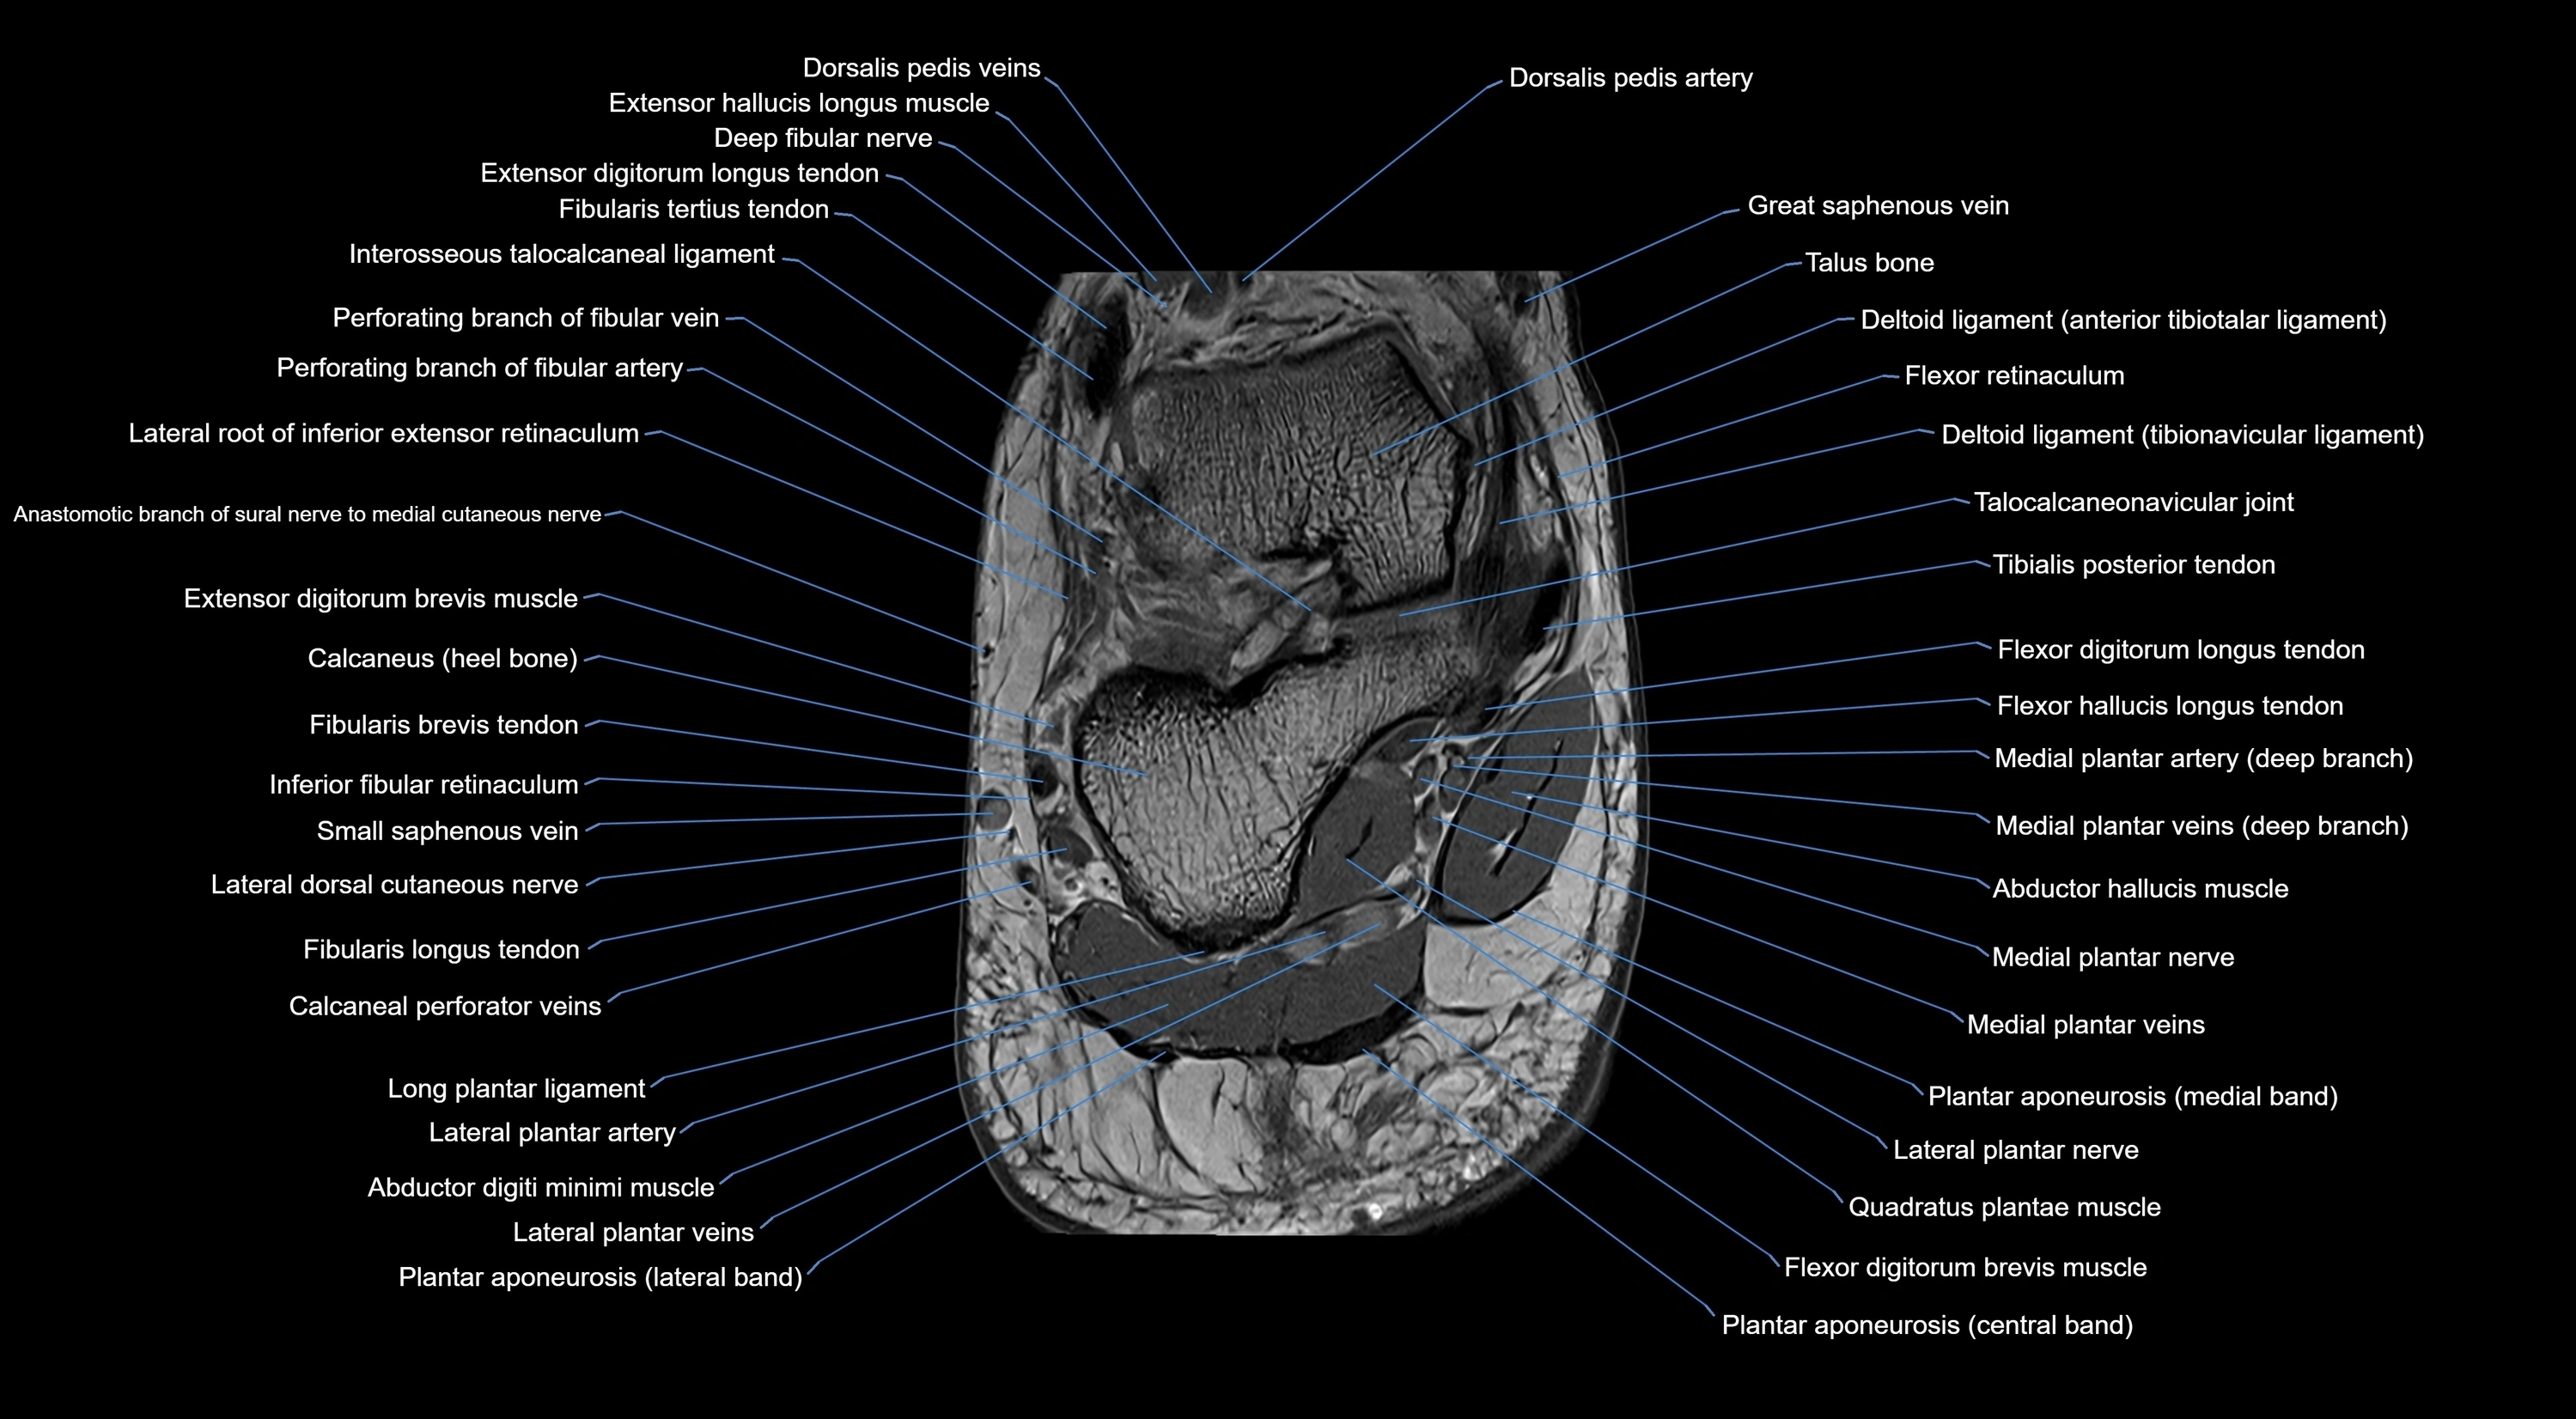

MRI image